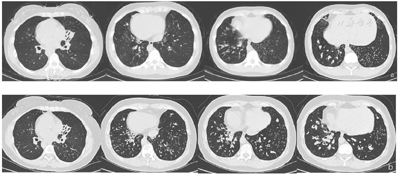

经鼻呼气一氧化氮:8bbp。肺功能提示中度阻塞性通气功能障碍,呼气峰流速下降,弥散功能正常。肺CT:内脏完全转位,双肺弥漫分布微结节,多发囊状扩张支气管,双肺下叶支气管管腔内可见高密度影填充,左肺中叶体积缩小,成三角形高密度影,2009年肺CT与2020年肺CT比较可见支气管扩张明显加重(图1)。鼻窦CT提示双侧上颌窦、筛窦、额窦、蝶窦内见密度增高影,慢性鼻炎(图2)。鼻内镜可见右侧中鼻道息肉组织。支气管镜检查可见主气道大量黏性分泌物,取支气管黏膜组织刷检送电镜检测可见部分纤毛外动力臂缺失及复合纤毛(图3)。高速视频显微镜下观察纤毛摆动频率减慢。采集全血标本,提取基因组DNA进行外显子基因检测,结果发现DHAH5基因63号外显子出现一个杂合突变,在10616号核苷酸由鸟嘌呤G变为腺嘌呤A(c.G10616A)的突变(箭头所示),导致第3539号氨基酸由精氨酸变为组氨酸(p.R3539H),见图4。该位点为国外已报道位点[7]。

Kartagener综合征属于PCD的一种亚型,研究发现Kartagener综合征约占PCD的50%,推测发生内脏转位是在胚胎发育中由于胚节纤毛功能障碍,使内脏出现转位或不转位的随机事件[8,9]。Kartagener综合征并不会在出生时即会表现所有临床症状,而是随着年龄增长,患者复发发生慢性咳嗽和呼吸道感染,临床症状逐渐典型。对于表现为完全型Kartagener综合征的患者(同时出现鼻窦炎、支气管扩张、内脏转位三联征),诊断相对容易,但确诊时间往往延迟。而不伴有内脏转位的PCD临床异质性较大,加之临床医生认识水平不足,极易出现漏诊和诊断延误[10],很多患者确诊时已进展至终末状态,早期确诊原发性纤毛运动障碍,尽早开始健康指导及肺康复锻炼对于改善患者预后极为重要。本例Kartagener综合征患者在年幼时常出现反复咳嗽咳痰症状,直至中年确诊。目前国内缺乏Kartagener综合征长期随访的肺功能及影像学数据,本研究首次对比了患者前后11年随访的肺CT变化,更直观地展示出疾病的进展的过程,特征的肺部病变影像为弥漫性分布,双下肺为主的囊性支气管扩张及粘液栓形成(图1ab)。